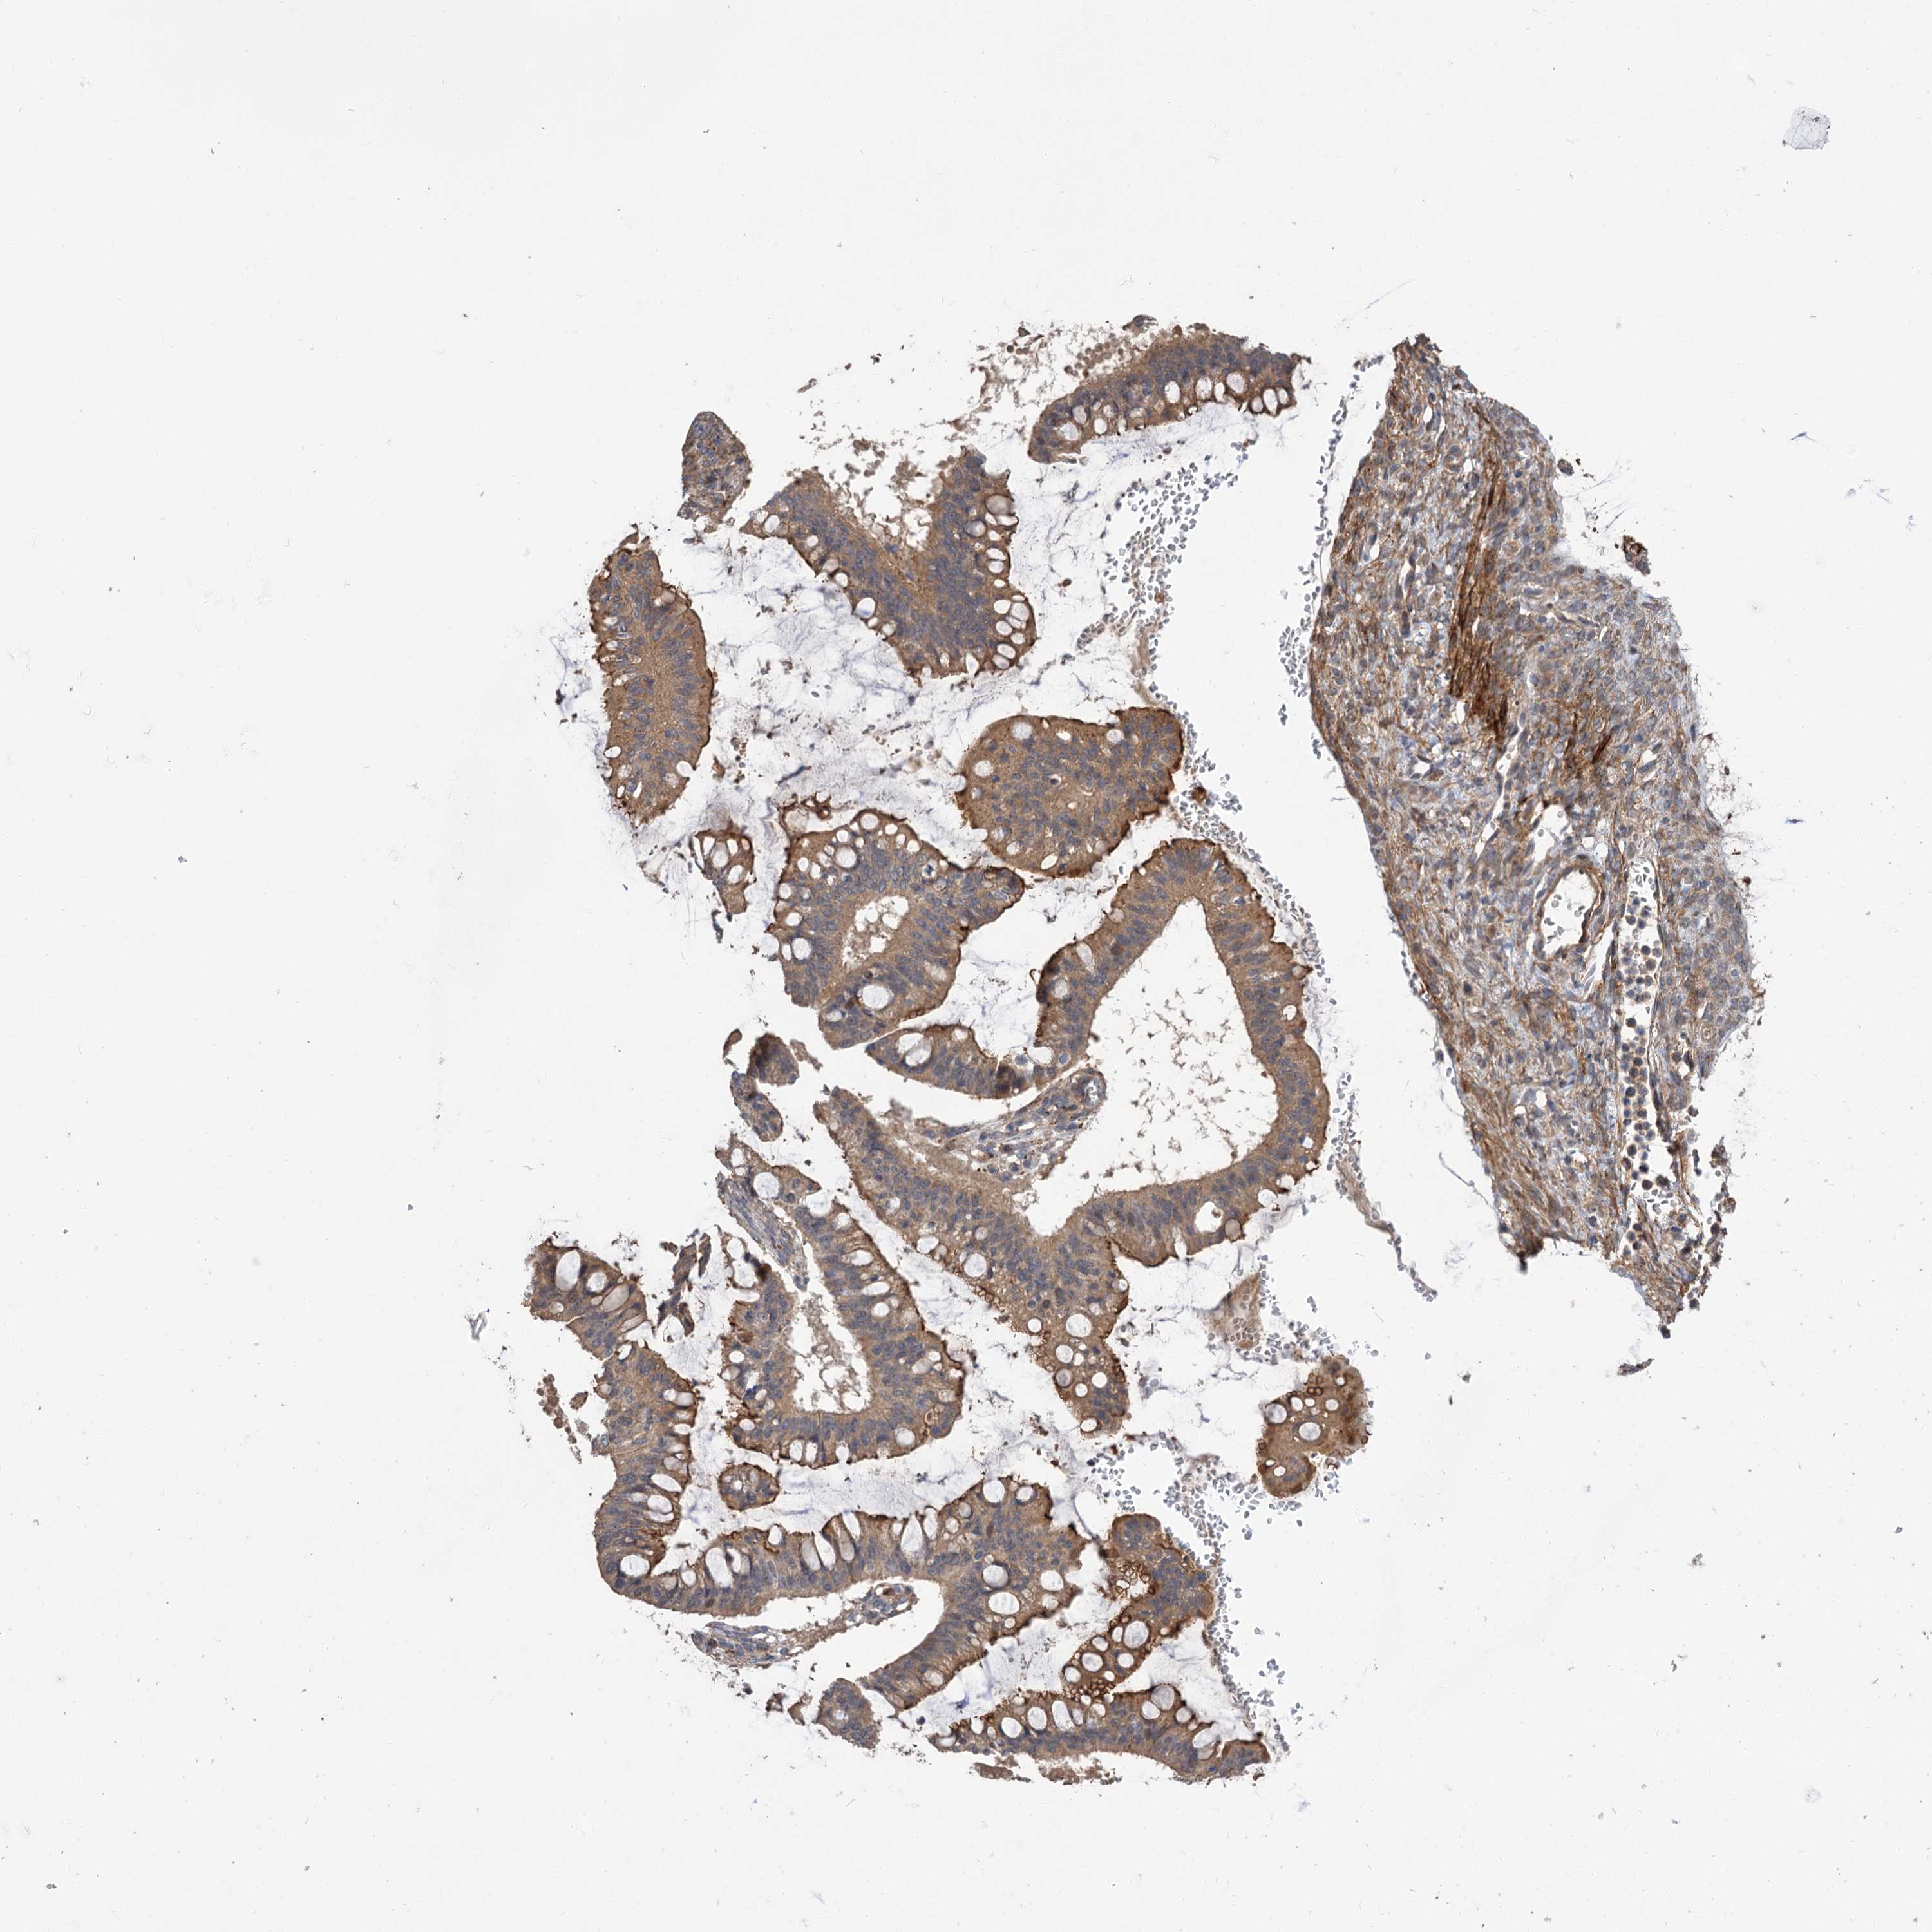

OVARIAN CANCER - Protein expressioni

A mouse-over function shows sample information and annotation data. Click on an image to view it in a full screen mode. Samples can be filtered based on level of antibody staining by selecting one or several of the following categories: high, medium, low and not detected. The assay and annotation is described here.

Note that samples used for immunohistochemistry by the Human Protein Atlas do not correspond to samples in the TCGA dataset.

Antibody stainingi

Antibody staining in the annotated cell types in the current human tissue is reported as not detected, low, medium, or high, based on conventional immunohistochemistry profiling in selected tissues. This score is based on the combination of the staining intensity and fraction of stained cells.

Each image is clickable and will lead to virtual microscopy that enables deeper exploration of all samples and also displays staining intensity scores, fraction scores and subcellular localization as well as patient and tissue information for each sample.

Antibody HPA038850

Antibody HPA038851

Carcinoma, NOS